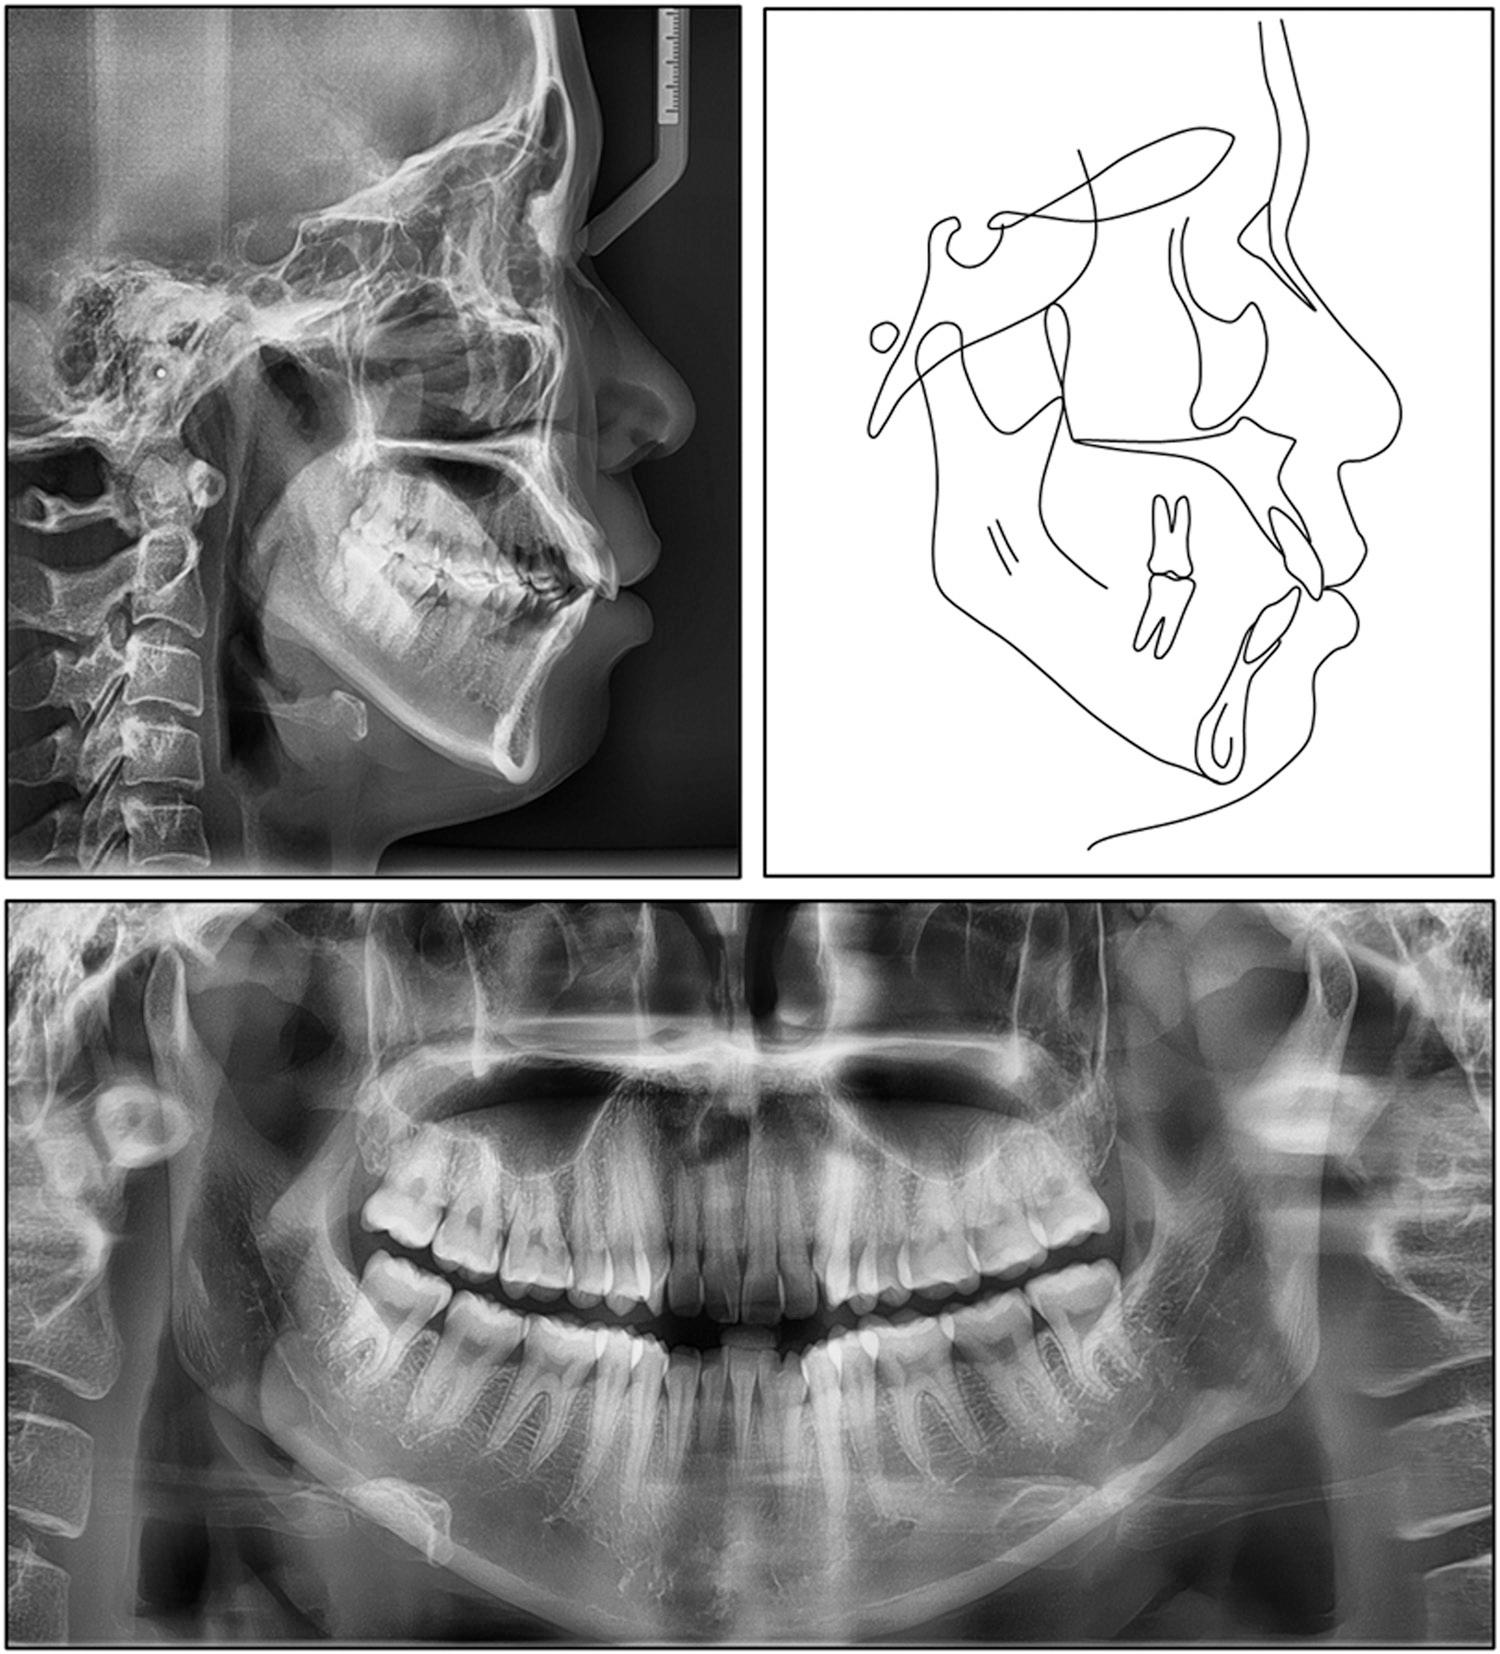

Figure 1.